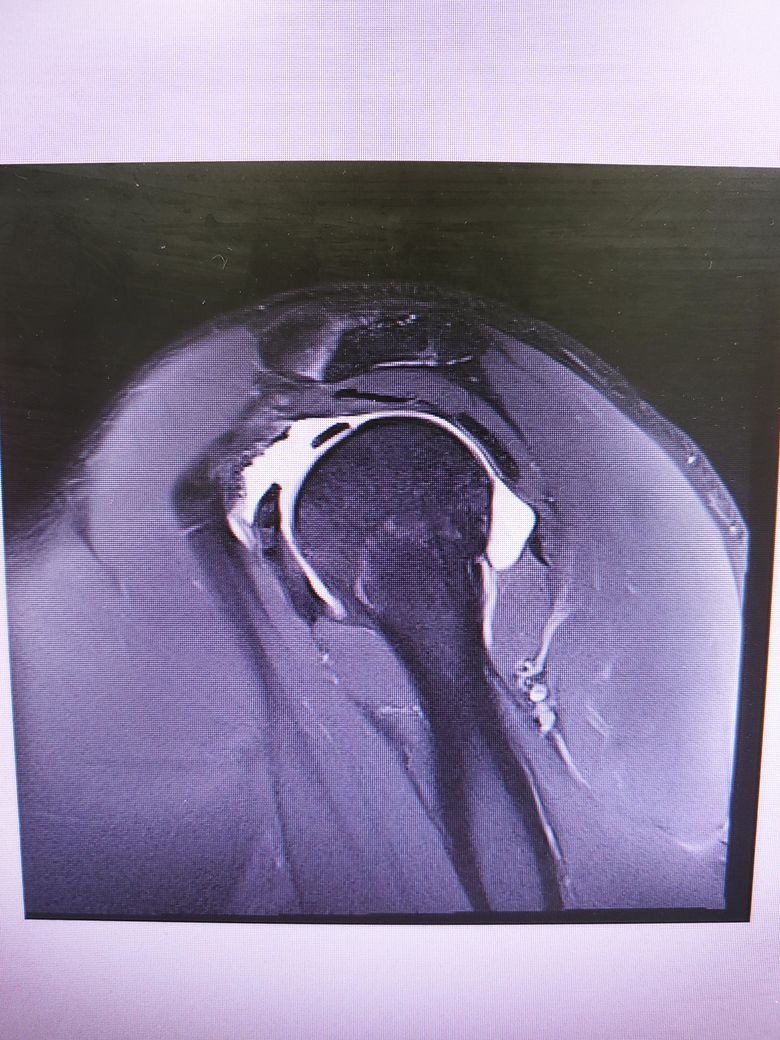

팔이 잡아당겨지는 사고 이후 통증이 지속되어

조영제 투입 후 mri 촬영을 하였습니다.

진단명은 상부관절와순파열(슬랩)이며

헬스와 같은 운동을 계속 하려면 수술이 필요하다 하였습니다.

슬랩이 맞나요? 맞다면 파열 진행 정도는 어느정도인지..

궁금합니다..최대한 사진 많이 올립니다 감사합니다..